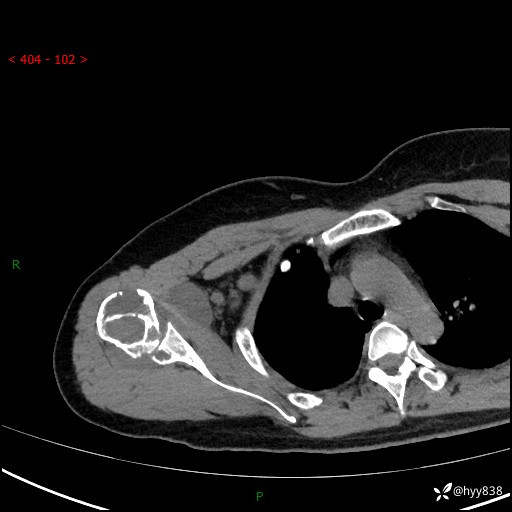

右肩关节平片

右肩关节CT平扫